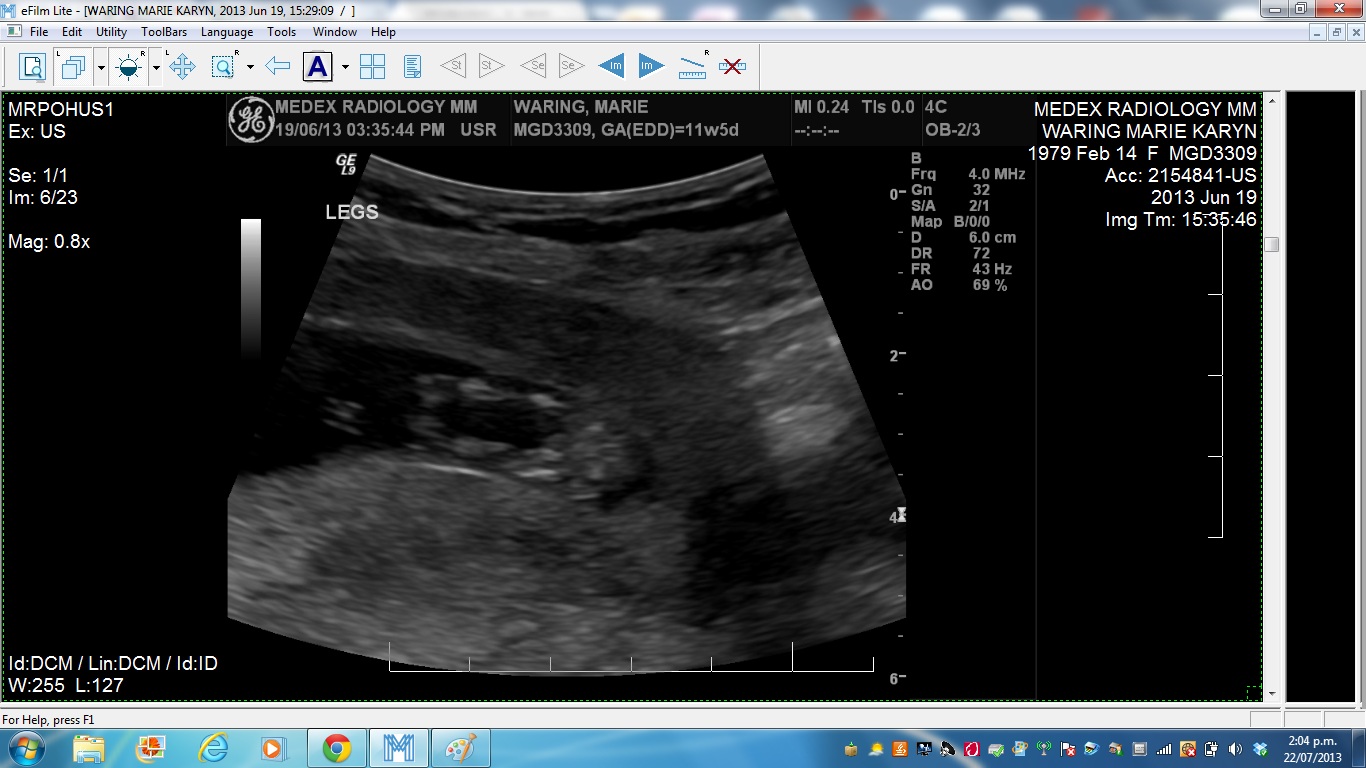

Attachment 12492

I didnt think there was much to see :-) I just posted pic number 5, there is something at the end but not sure if its a "nub" (its split??)

leaning boy off your last pic.

Yeah, new pic leans me more blue :)